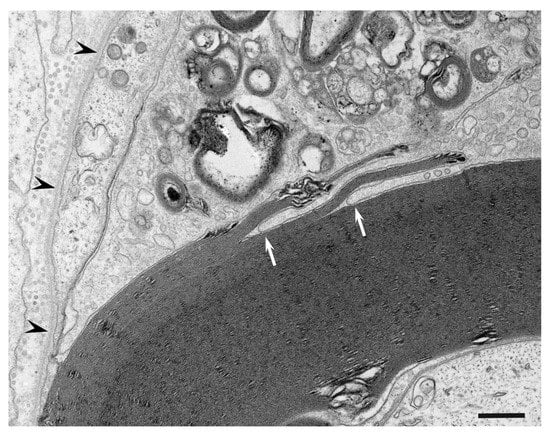

- Koike, H.; Nishi, R.; Ikeda, S.; Kawagashira, Y.; Iijima, M.; Katsuno, M.; Sobue, G. Ultrastructural mechanisms of macrophage-induced demyelination in CIDP. Neurology 2018, 91, 1051–1060. [Google Scholar] [CrossRef]

- Koike, H.; Fukami, Y.; Nishi, R.; Kawagashira, Y.; Iijima, M.; Katsuno, M.; Sobue, G. Ultrastructural mechanisms of macrophage-induced demyelination in Guillain-Barré syndrome. J. Neurol. Neurosurg. Psychiatry 2020, 91, 650–659. [Google Scholar] [CrossRef]

- Koike, H.; Katsuno, M.; Sobue, G. Deciphering the mechanism and spectrum of chronic inflammatory demyelinating polyneuropathy using morphology. Clin. Exp. Neuroimmunol. 2018, 9, 35–46. [Google Scholar] [CrossRef]

- Koike, H.; Katsuno, M. The role of macrophages in Guillain-Barré syndrome and chronic inflammatory demyelinating polyneuropathy. Neurol. Clin. Neurosci 2021, in press. [Google Scholar] [CrossRef]